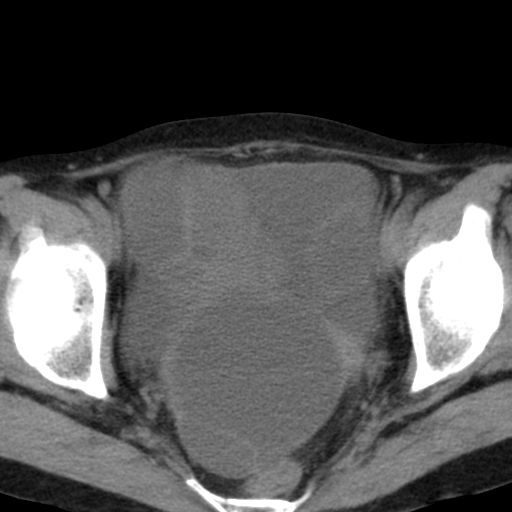

女,70,腹部间断性胀痛三月余

子宫宫腔及双侧附件积液,原因?

考虑卵巢囊腺瘤,不排除囊腺癌。

考虑卵巢囊腺瘤或囊腺癌。实质成分太多,考虑后者可能性大.

年龄较大还是恶性可能大,不排除库肯勃瘤

双侧卵巢粘液性囊腺癌,不多赘述。

考虑卵巢囊腺瘤;囊腺癌不能排除(理由:病人年龄较大,病灶外形欠规整、囊实相间,实性成分较多均支持囊腺癌)。要是能听听九目段老师的点评就好了!

年龄较大,囊实相间,实性成分较多均支持囊腺癌。

考虑囊腺癌,子宫病变不能排除吧,建议mri检查。